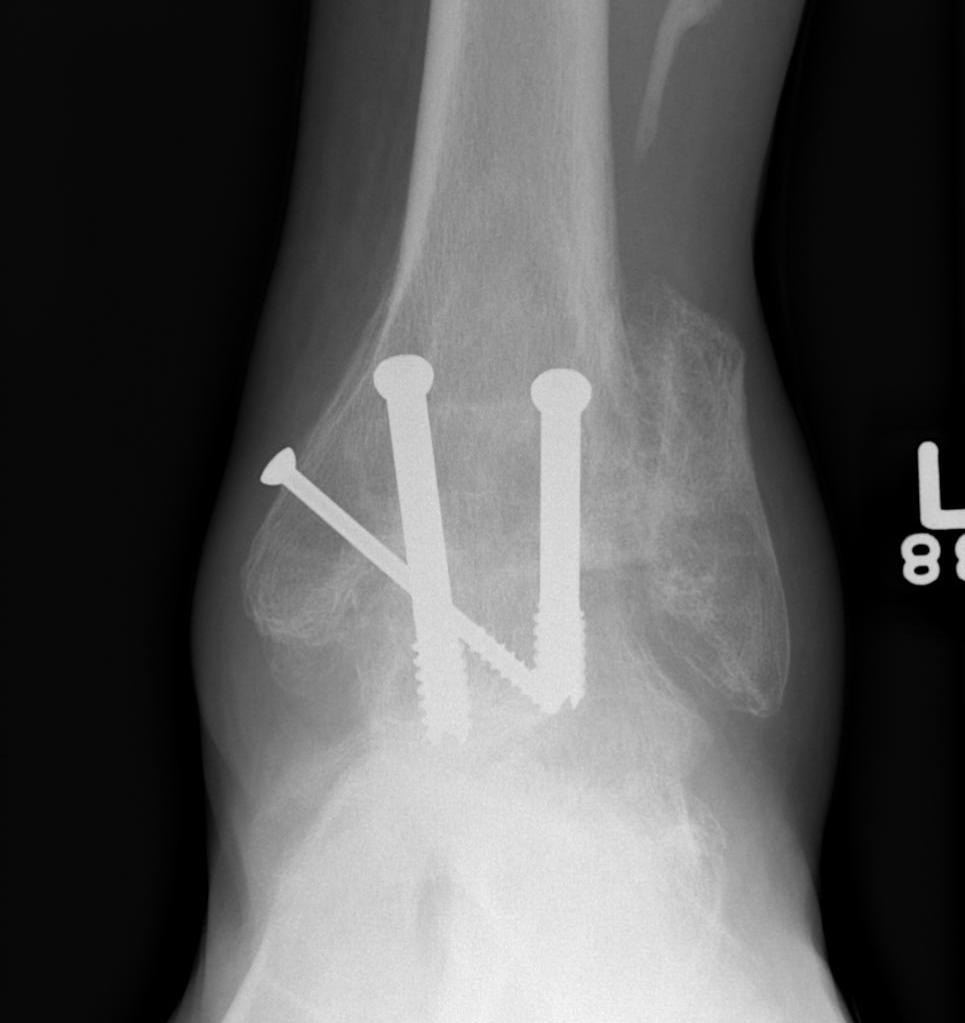

- two cannulated screws from medial tibia to talus dome / neck

- +/- screw medial malleolus to talus

- +/- screw fixation fibular / onlay graft

- fix with 3 x 6.5 mm cannulated screws

- 2 medial and one lateral